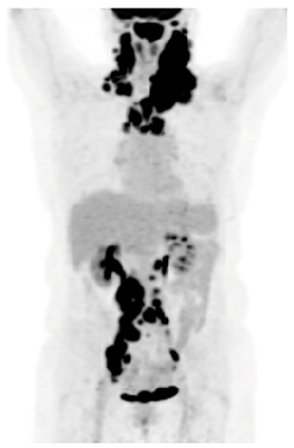

PET/CT: lymphadenopathy above and below diaphragm, (maximum 14 cm)

Complete response on post-treatment PET/CT

PET/CT and biopsy confirmed recurrent DLBCL